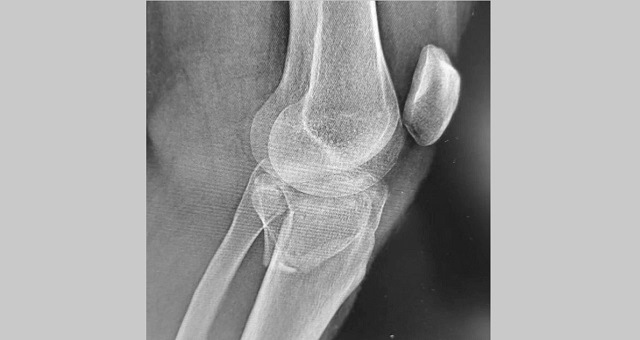

В Казани врачи горбольницы №7 прооперировали мужчину, который в результате падения с самоката получил многооскольчатый перелом верхнего суставного конца большеберцовой кости с разрывом боковых связок.

В ходе операции медики выполнили остеосинтез пластинами и винтами, а также восстановили связки коленного сустава. По словам медиков, самокат в последнее время стал популярным средством попадания в травматологическое отделение.